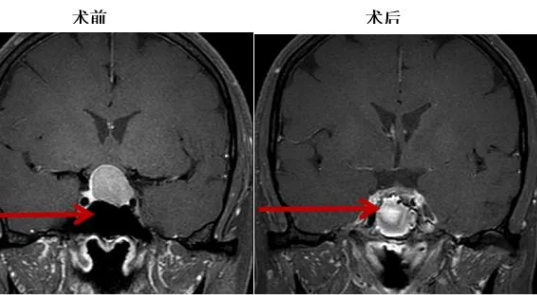

近日,有一93岁高龄男性患者普某某,“跌伤头部伴头晕、头痛、左下肢乏力2周”在外院因高龄、治疗风险高而辗转多家医院,于不久前通过红河州第三人民医院创伤中心经绿色通道收到该院神经外科,诊断为“右侧额颞顶部亚急性硬膜外血肿”。